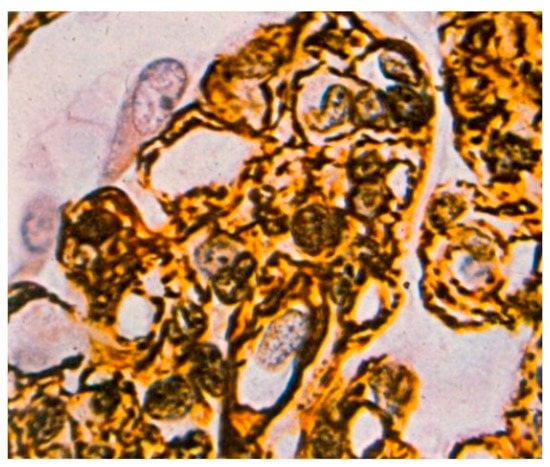

Light microscopy showed an increased number of cells in the glomeruli and an adventitia of the mesangial matrix. The kidney glomeruli were characterized by a lobular structure (Figure 4). Jones’ stain method highlighted the double-contouring of the capillary loop walls (Figure 5).

Figure 4. Kidney glomerulus with an increased number of cells and a well-defined lobular structure. H&E, 100× magnification.